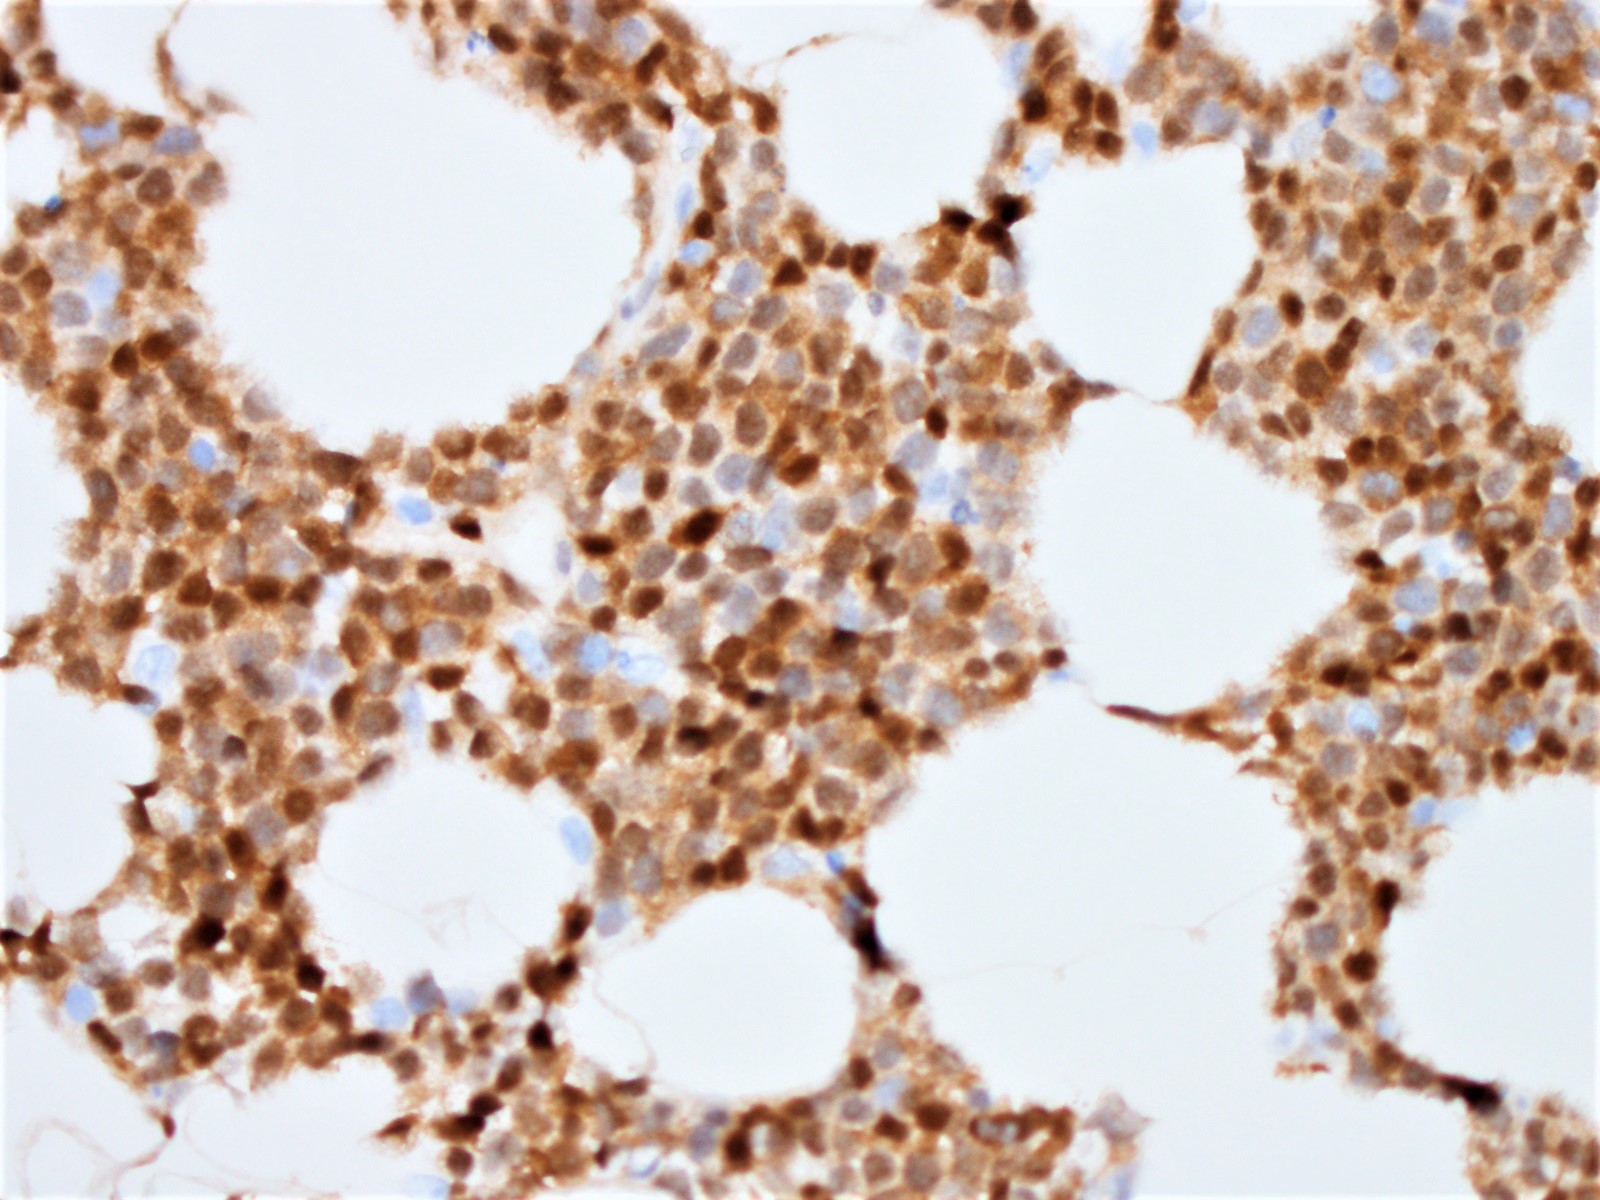

Microscopic (histologic) images

Positive stains

- Immunophenotype similar to classic mantle cell lymphoma

- CD19, CD20, CD43, sIg, IgM with or without IgD

- CD5 (> 95%), SOX11 (> 90%)